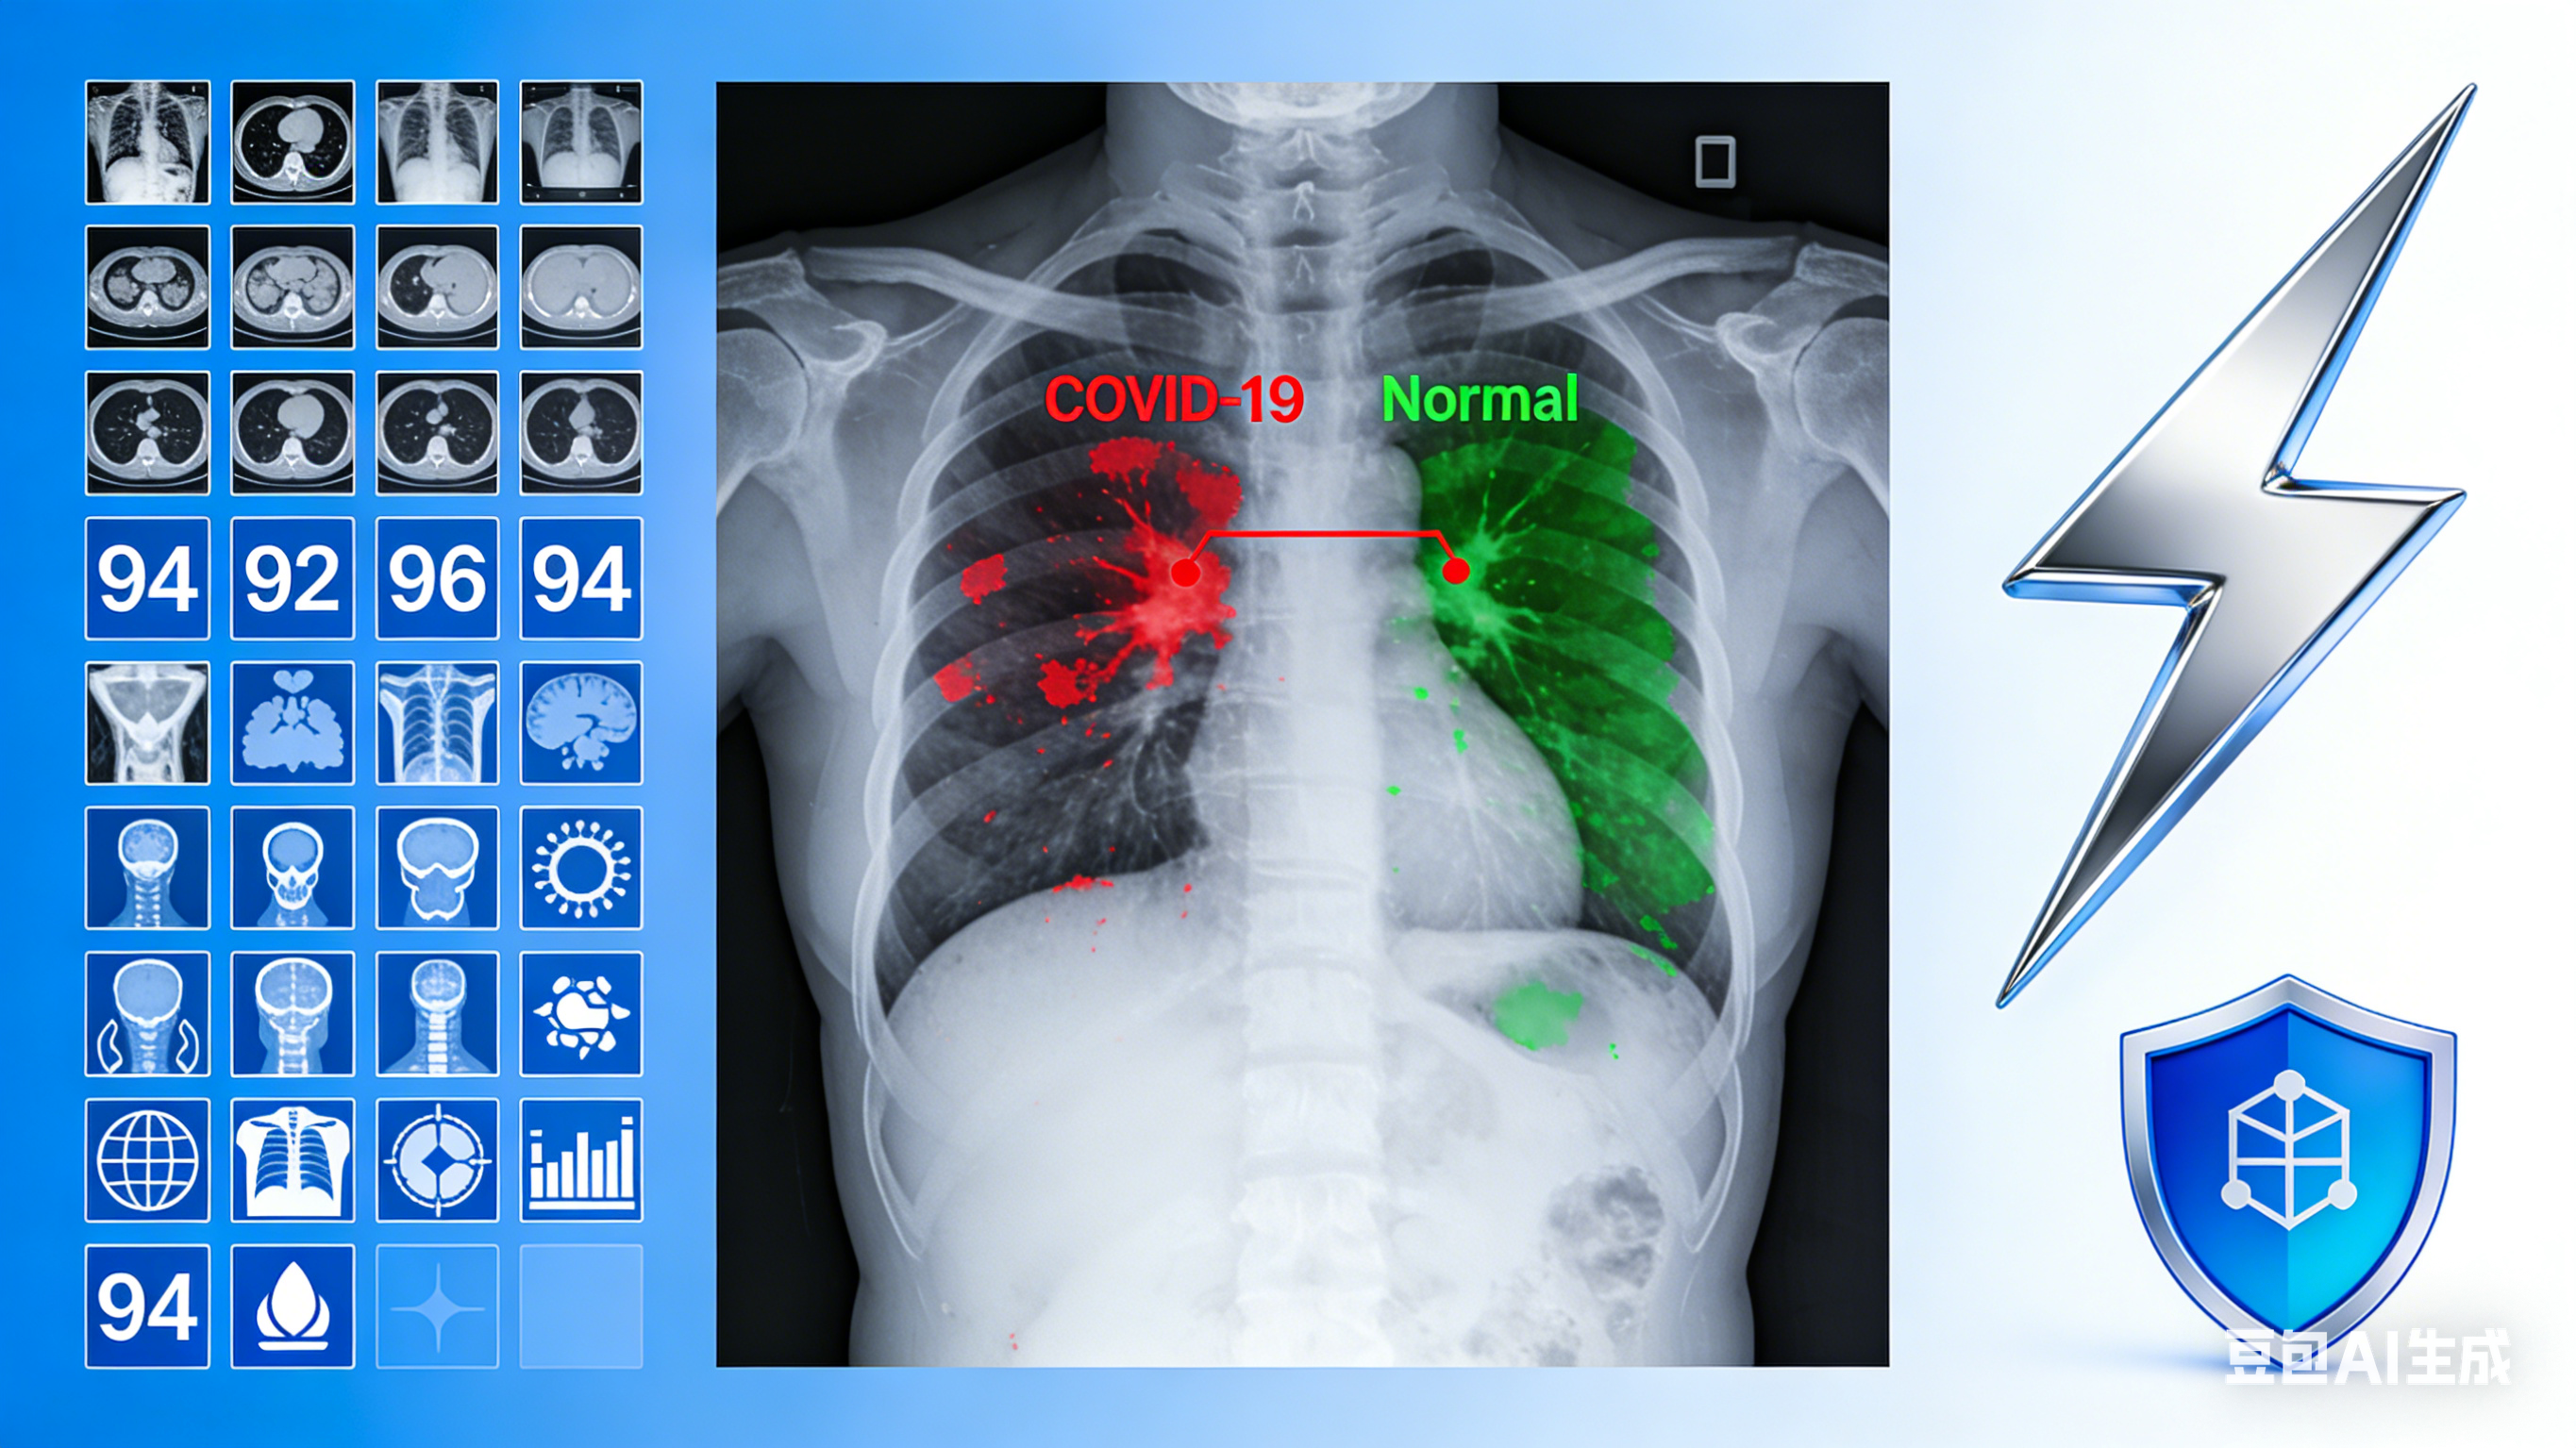

新型冠状病毒肺炎(COVID-19)自2019年底爆发以来,已成为全球公共卫生领域的重大挑战。胸部X光检查作为一种快速、无创的影像学诊断手段,在COVID-19的早期筛查、诊断和治疗监测中发挥着重要作用。随着人工智能技术的快速发展,基于深度学习的医学影像分析成为辅助临床诊断的有效工具,而高质量的标注数据集是训练和评估这些模型的基础。

基于本数据集,可以开发COVID-19胸部X光图像自动诊断系统。通过深度学习算法对图像进行分析,提取COVID-19特征(如磨玻璃影、实变影等),辅助医生进行快速筛查和诊断。该系统可以显著提高诊断效率,减少医护人员的工作负担,尤其在疫情爆发期间能够发挥重要作用。

医学教育和培训

该数据集可以作为医学教育和培训的重要资源,帮助医学生和临床医生学习COVID-19的胸部X光影像学表现。通过对比COVID-19阳性和正常胸部X光图像,加深对疾病影像学特征的理解,提高诊断水平。